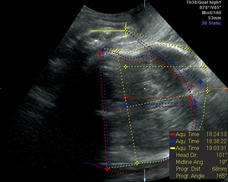

GE公司的SonoVCAD labor技术是基于三维容积超声的计算机辅助产程监测软件。利用三维超声多平面成像技术,可同时显示相交平面,增加了更多信息,使得测量的切面更为准确,重复性佳[5]。软件可在三维容积数据的不同平面自动测量出相应的胎头方向角(图1)、胎头进展角(图2)、胎头下降距离(图3)及中线角(图4)这四个参数,并在产程中动态观察各参数的变化,利用软件记录产程的全过程(图5),从而监测第二产程进展。

图2. 在A平面,从耻骨联合到胎头边缘画一条切线,胎头进展角为这条切线和耻骨联合中间部分的水平线的夹角